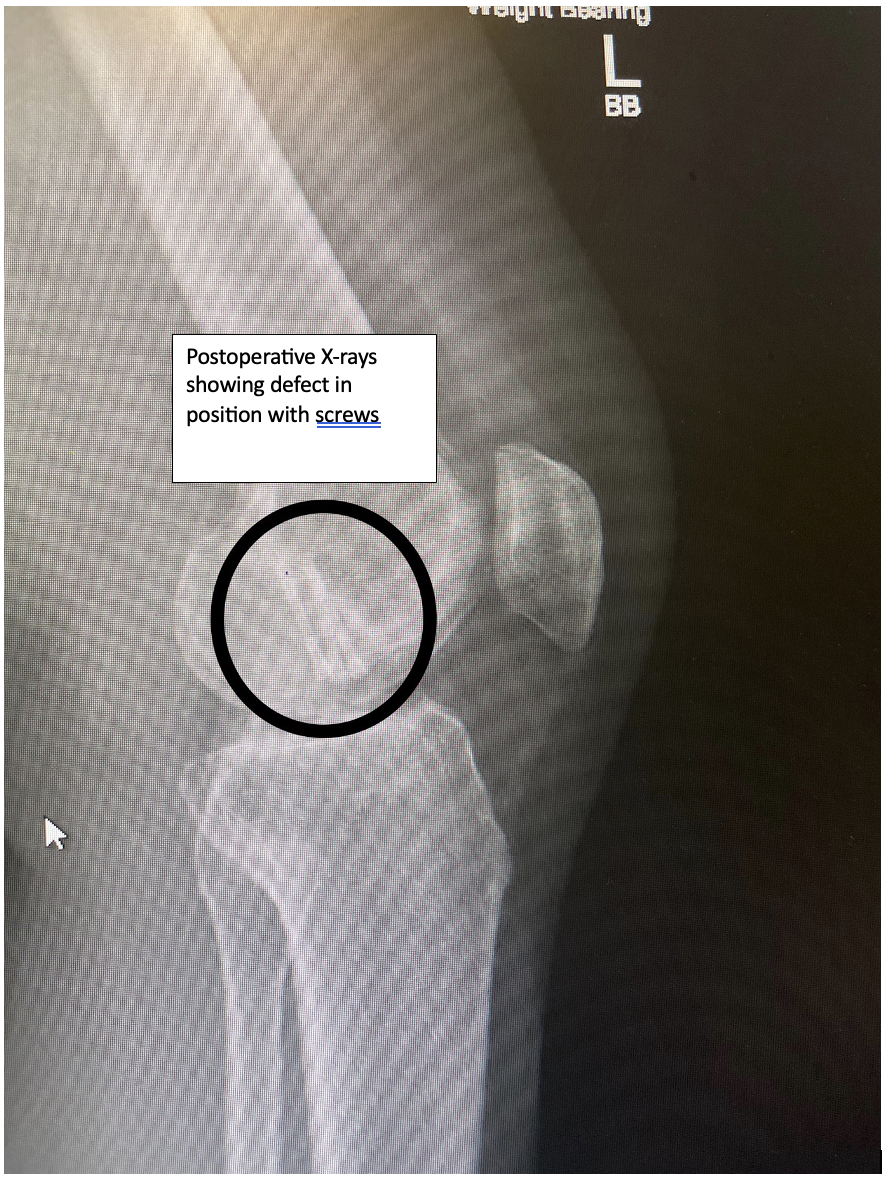

Example of bone fixed back with metal screws.

Defect fixed back into position with metal screws: